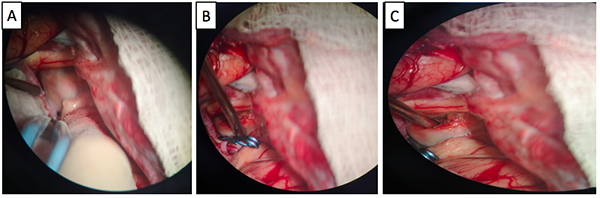

Luego del análisis del caso, y teniendo en cuenta la presencia del trombo intracavitario, el cuello del aneurisma, la posición favorable del saco aneurismático, y la edad de la paciente, se decidió que la cirugía era la mejor opción terapéutica, se realizó una craneotomía pterional derecha, y un abordaje transilviano bajo visión microscópica. Se encontró un aneurisma de gran tamaño dependiente de la AcomA (Figura 2), con dirección anteroinferior, calcificación en las paredes del domo y signos de trombosis. Una vez se identificó el cuello, y ambas A1 y A2, se posicionó un clip recto de 9 mm, que luego se reacomodó con otro clip definitivo de 9 mm, se retiró el previamente colocado, quedando con un solo clip definitivo. A continuación se comprobó la permeabilidad de los vasos A1 y A2, así como de la arteria recurrente de Heubner ipsilateral con doppler intraoperatorio. Se procedió con la disección del domo del aneurisma y trombectomía con aspirador ultrasónico, dejando el interior del aneurisma friable, y descomprimiendo de esta manera el nervio y el quiasma óptico. El procedimiento finalizó sin complicaciones, la paciente mejoró del déficit en el postoperatorio inmediato, y se llevó a arteriografía de control al día siguiente de la intervención, con la que se confirmó el adecuado clipaje de la lesión (Figura 3).

Figura 2 Secuencia quirúrgica. Se exponen los pasos más importantes. Disección de estructuras alrededor del aneurisma, el punto blanco señala el cuello del aneurisma expuesto y en azúl el domo (A). Clipaje del cuello (B). Aneurismectomía y trombectomía. La marca de color azúl indica el lóbulo temporal izquierdo, en blanco se observa el lóbulo frontal, y debajo de este se encuentra el aneurisma de ACoA abierto, por encima del domo marcado en color negro se puede observar el nervio óptico, y adyacente a este, en color rojo, se observa la arteria carótida interna, detrás del domo del aneurisma y en color amarillo, la arteria cerebral anterior izquierda cursa paralela al cuello del aneurisma (C)